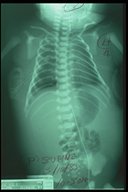

Chest X-ray of a "hydrops fetalis" baby soon after birth. The baby was prenatally diagnosed of bilateral chylothorax. Haziness were noted over both lung fields.